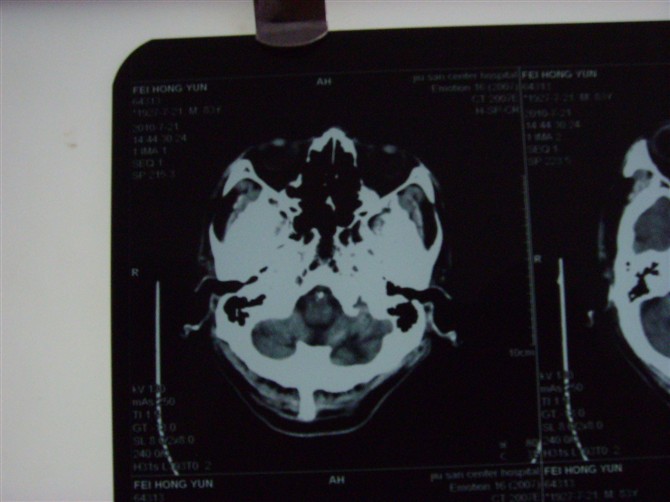

标题: CT27993:男 83岁 头晕伴双下肢无力一天 [打印本页]

标题: CT27993:男 83岁 头晕伴双下肢无力一天

脑萎缩。伴小脑齿状核、苍白球钙化。必要是mri进一步检查。

脑萎缩。伴小脑齿状核、苍白球钙化.脑白质脱髓鞘病变

脑白质变性、脑萎缩。甲状旁腺功能减退。

1)双侧小脑半球脑软化灶。2)全脑萎缩。3)脑白质病。